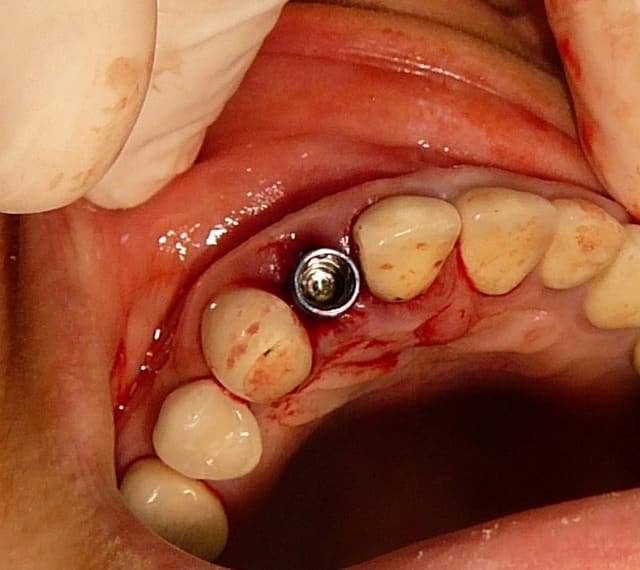

non, je note seulement les références du pilier.

le prothésiste commande un pilier identique en forme , mais en zircone (pour les antérieurs en tout cas), et reproduit au mieux l'émergence de ma provisoire. le pilier initial sera réutilisé pour quelqu'un d'autre...

une fois positionnée en bouche, je remet la courone sur le pilier que je démonte et réalise l'émergence avec le flow.

c'est assez précis et propre.

ici, c'est un implant AXIOM, le diamètre à la sortie du col de l'implant est très fin (cône et platform switching) et permet donc de travailler l'émergence au mieux.

je dis cela car sur les autres type d'implants avec une connexion plate, l'utilisation d'un pilier personnalisé est plus souvent nécessaire.